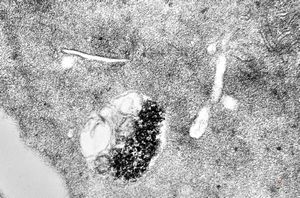

F,43y. | blood - leukemia - bacteriaemia - phagocytosed microbes

phagocytosed microbes

M,2w. | bacteriaemia - phagocytosed microbes

phagocytosed microbe